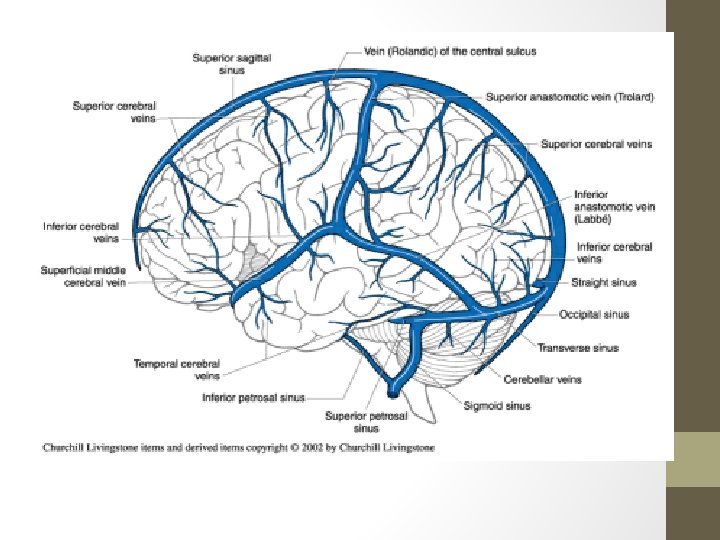

Superficial Venous System • Comprised of the sagittal sinuses and cortical veins. • The cortical veins course along the cortical sulci, drain the cortex and some of the adjacent white matter. • Can be subdivided into superior, middle and inferior groups. • Important veins of superficial cerebral venous system; -Superficial middle cerebral vein -Superior anastomotic vein of Trolard -Vein of Labbé

Superficial Middle Cerebral Vein • Runs along the lateral sulcus-also known as Sylvian Vein • Drains into the sphenoparietal sinus or cavernous sinus • Connected with superior sagittal sinus via great anastomotic vein of Trolard, and with transverse sinus via posterior anastomotic vein of Labbé.

Vein Of Labbé • Largest channel that crosses the temporal lobe between the Sylvian fissure and the transverse sinus • Surgically it is of importance in planning temporal lobectomy for refractory temporal epilepsy, as the vein should be preserved, often requiring some cortical tissue to be left behind. This is especially the case in the 10% of cases where the vein is located anteriorly.

Deep Cerebral Veins • Drain deeper parts of hemispheres, basal nuclei, internal capsule, diencephalon and choroid plexus • Consists of the lateral sinuses, sigmoid sinuses, straight sinus and draining deep cerebral veins (subependymal and medullary veins) -Medullary veins are numerous and originate 1 -2 cm below cortical gray matter and pass through deep medullary white matter and drain into subependymal veins. -Subependymal veins receive medullary veins and aggregate into greater tributaries, mainly into septal veins, thalamostriate veins, internal cerebral veins, basal vein of Rosenthal and vein of Galen.